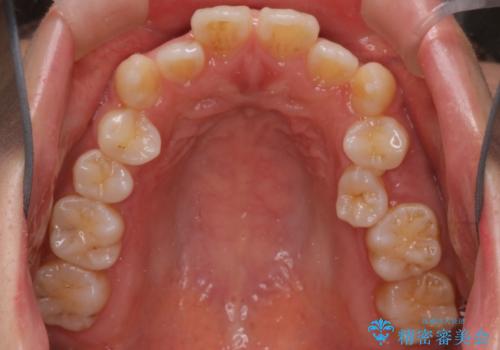

- 患者様は歯並びの乱れを気にされて来院されました。特に小臼歯の捻転(ねじれ)が強く、見た目だけでなく噛み合わせにも影響がありました。できるだけ目立たない方法を希望されていたため、インビザライン(マウスピース矯正)を基本としつつ、より精密な動きが必要な部分にはワイヤー矯正を併用する計画を立てました。また、小臼歯の捻転については**部分矯正(MTM:Minor Tooth Movement)**を取り入れ、効率的に改善を目指しました。

まず、全体の歯並びを整えるためにインビザラインを使用し、徐々に理想的な位置へと歯を移動させました。一方で、ねじれの強い小臼歯に対しては、**部分的なワイヤー矯正(MTM)**を行い、より精密なコントロールを実施。約2年の治療期間を経て、歯並びと噛み合わせが整い、見た目の美しさだけでなく、機能的な改善も達成しました。患者様からは「自然な仕上がりで、自信を持って笑えるようになった」と喜びの声をいただきました。